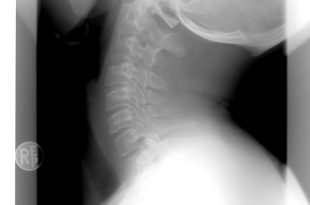

Omurga omur (vertebra) adı verilen 33-34 kemikten oluşur. Kafatasının hemen arkasından başlayıp kuyruk sokumuna kadar uzanır.